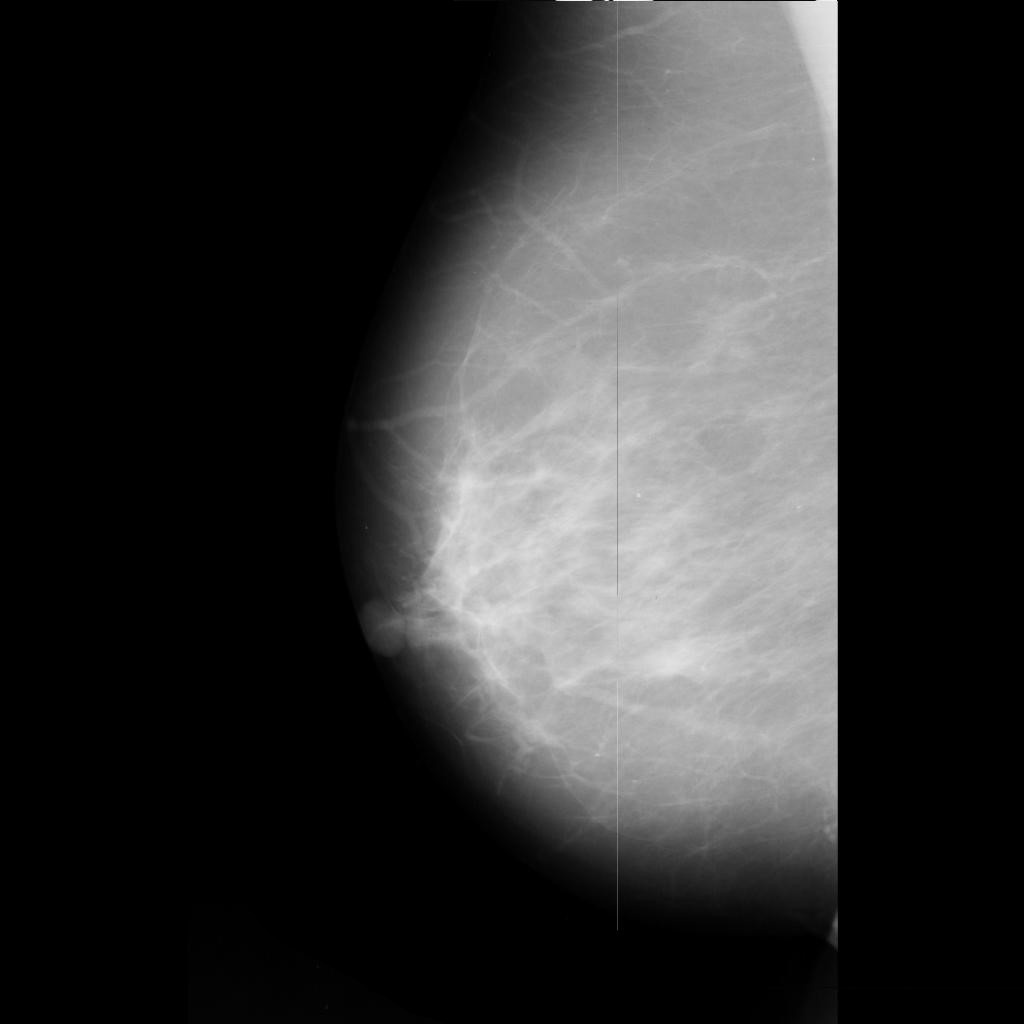

benign